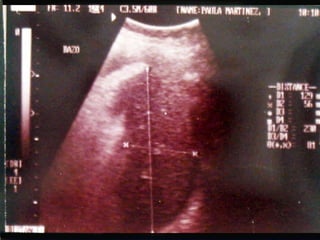

SONOGRAMA ABDOMINAL EVALUACIÓN HIGADO SISTEMA BILIAR BAZO  RIÑONES PANCREAS ( no específico)

SONOGRAMA ABDOMINAL EVALUACIÓN TAMAÑO ( Hepatitis, I.C.C., Cirosis) FORMA (lobular en cirrosis) LOCALIZACIÓN ( de masas) PATRON SONOGRÁFICO ( hiperecoico gris)

SONOGRAMA ABDOMINAL EVALUACIÓN HIPERTENSIÓN PORTAL : Aumento del diámetro de la porta (vena mesentérica y esplénica) aumento de calibre que no cambia con la respiración. Esplenomegalia Ascitis